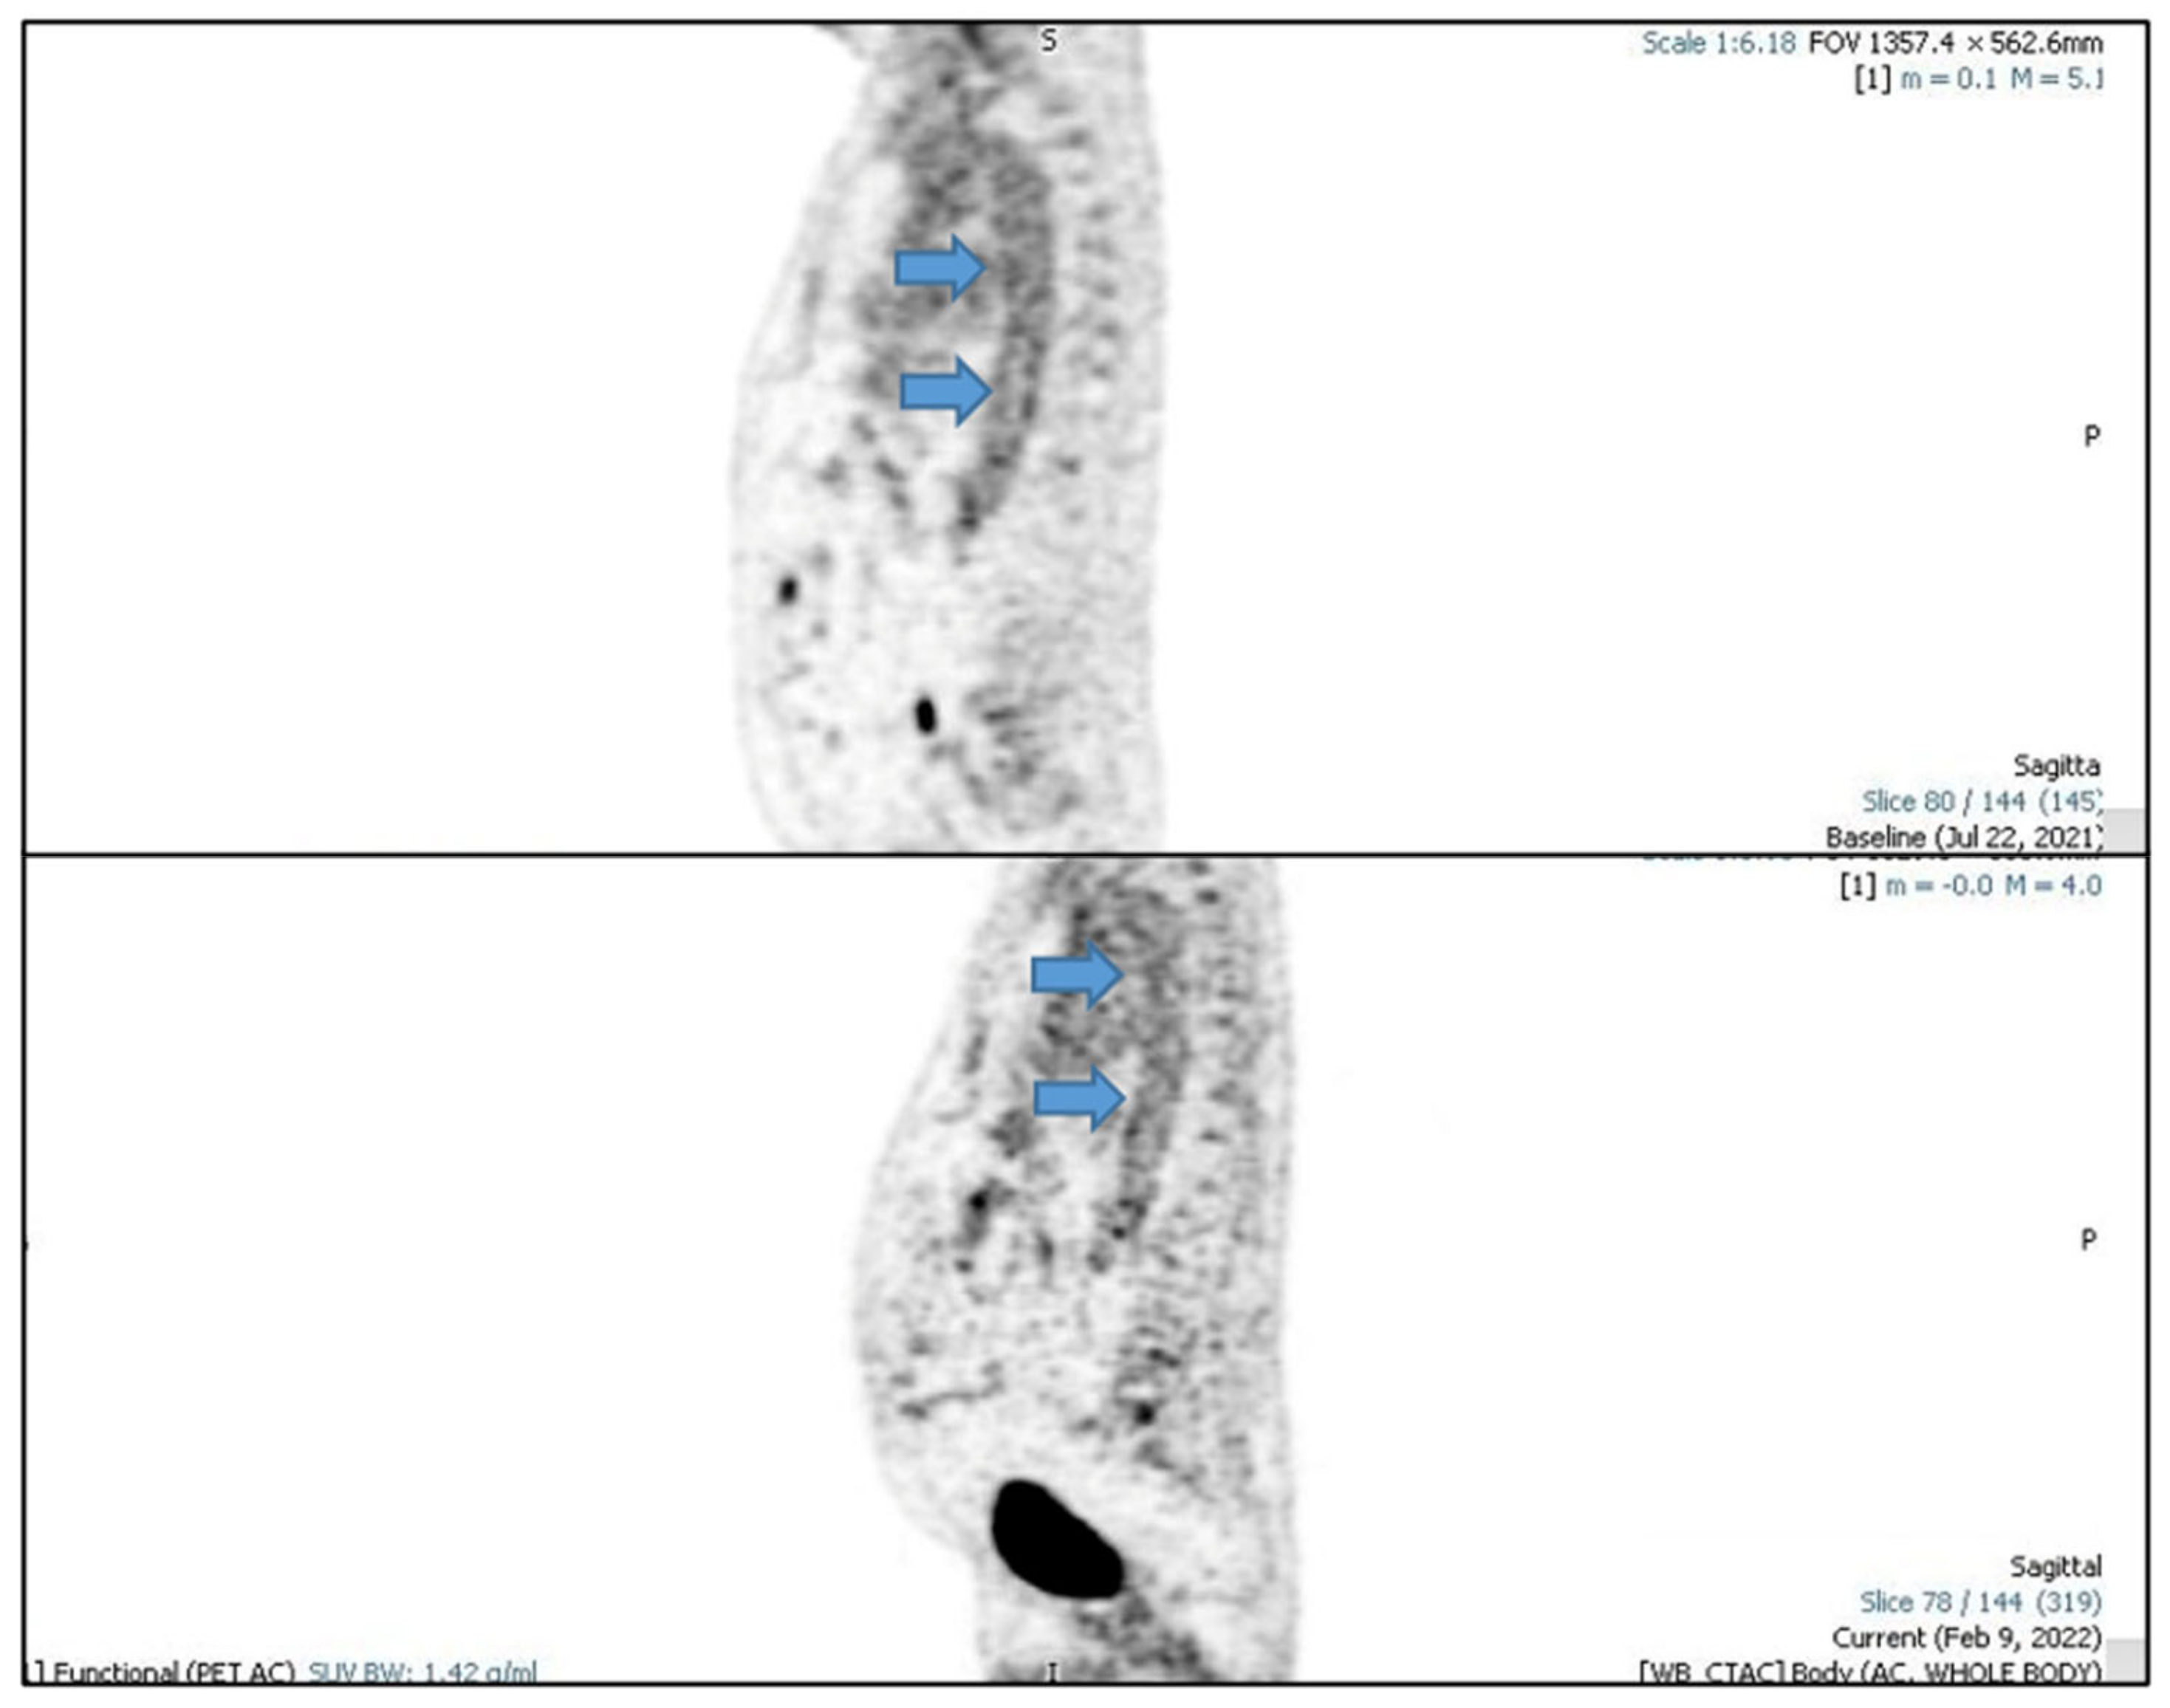

2. Case Report